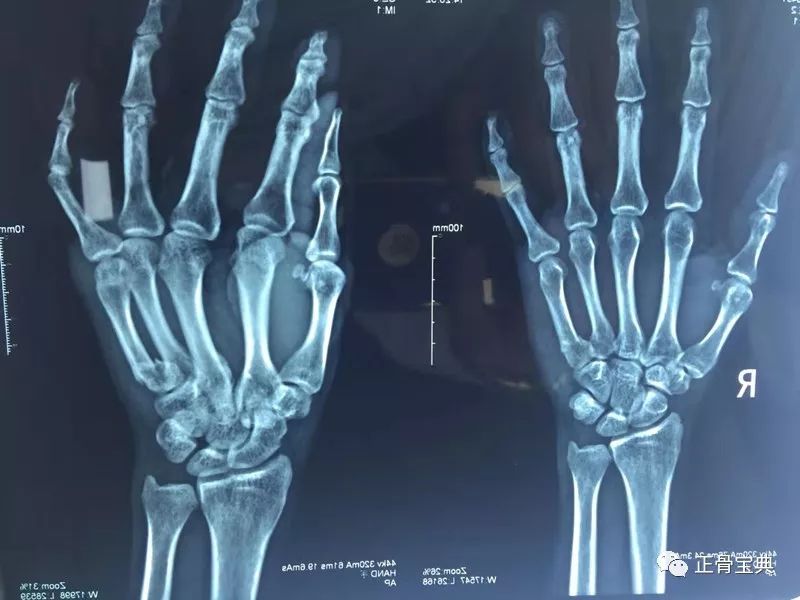

正骨宝典 92 第五掌骨基底部骨折 蔡天金正骨53 正骨宝典 微信公众号文章阅读 Wemp